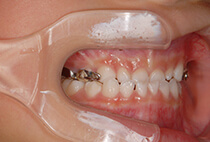

20代女性の患者さま。

八重歯の見た目が気になってご来院されましたが、実は顎の痛みや開口障害など、顎関節症の症状もありました。

そのため、かみ合わせと顎関節症の治療を同時に行ったにもかかわらず、2年間で治療が終了。

しっかり前歯を下げるために、インプラントアンカーを使用してコントロールしました。

かみ合わせが整うと咬筋の過緊張が改善。

過緊張による筋肉肥大も改善しフェイスラインもすっきりしました。

治療前

治療後